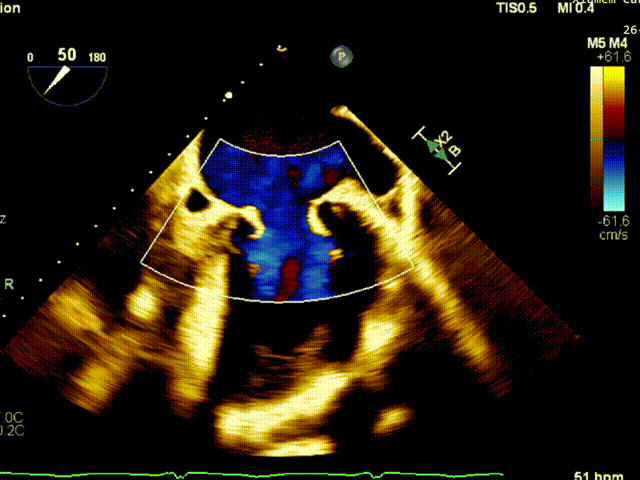

术前TEE评估

经食道超声提示,患者二尖瓣P1 commissural脱垂、腱索断裂合并重度反流(Carpentier II型/DMR4+)。

二尖瓣后瓣环明显钙化;主动脉瓣轻度钙化;三尖瓣中度功能性反流(FTR2+)。左房明显扩大;左室壁非对称性肥厚,以室间隔基底段肥厚为著(HOCM)。左室整体收缩功能正常。

二尖瓣环AP径33mm,二尖瓣后瓣环明显钙化,房间隔拟穿刺高度40mm;二尖辦脱垂宽度5.7mm,脱垂高度7.7mm,二尖瓣1区前叶长度29mm,后叶长度19mm,二尖瓣2区前叶长度23mm,后叶长度14mm,MVA=4.0cm²。

术前1区X-Plane反流情况